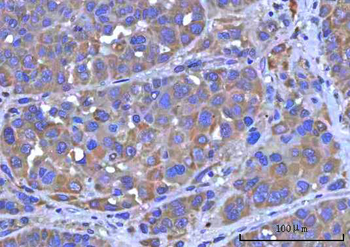

IHC staining of FFPE human lymph node with CD72 antibody (clone BU40). HIER: boil tissue sections in pH9 10mM Tris with 1mM EDTA for 20 min and allow to cool before testing.

IHC staining of FFPE human lymph node with CD72 antibody (clone BU40). HIER: boil tissue sections in pH9 10mM Tris with 1mM EDTA for 20 min and allow to cool before testing.